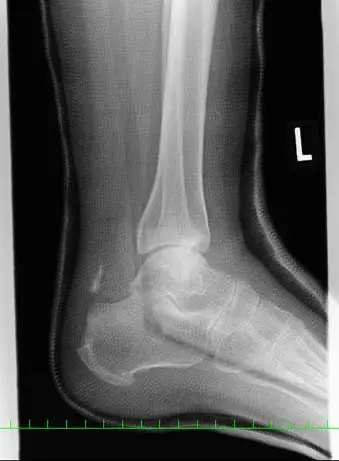

(図1)単純レントゲン像

足関節内外果、脛骨天蓋部に骨折と踵骨アキレス腱付着部より1.5cm近位に骨片を認める。